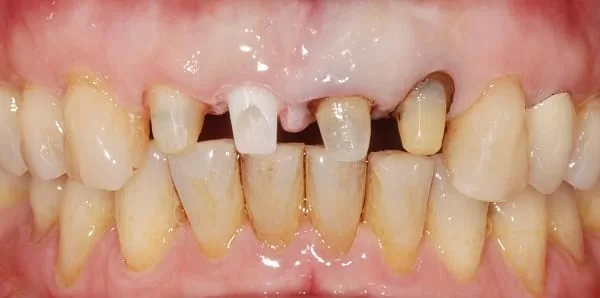

左上兩顆門牙,有牙套不密合之情況。 經仔細評估後,決定拔除並立即植牙(即拔即種,圖2);

另可看到,左上側門牙的牙根已被之前的金屬牙套染成黑色(圖4)。

(圖3: 治療前4顆門牙為臨時假牙)

(圖4: 三個月後使用氧化鋯柱心, 預備做固定牙套)